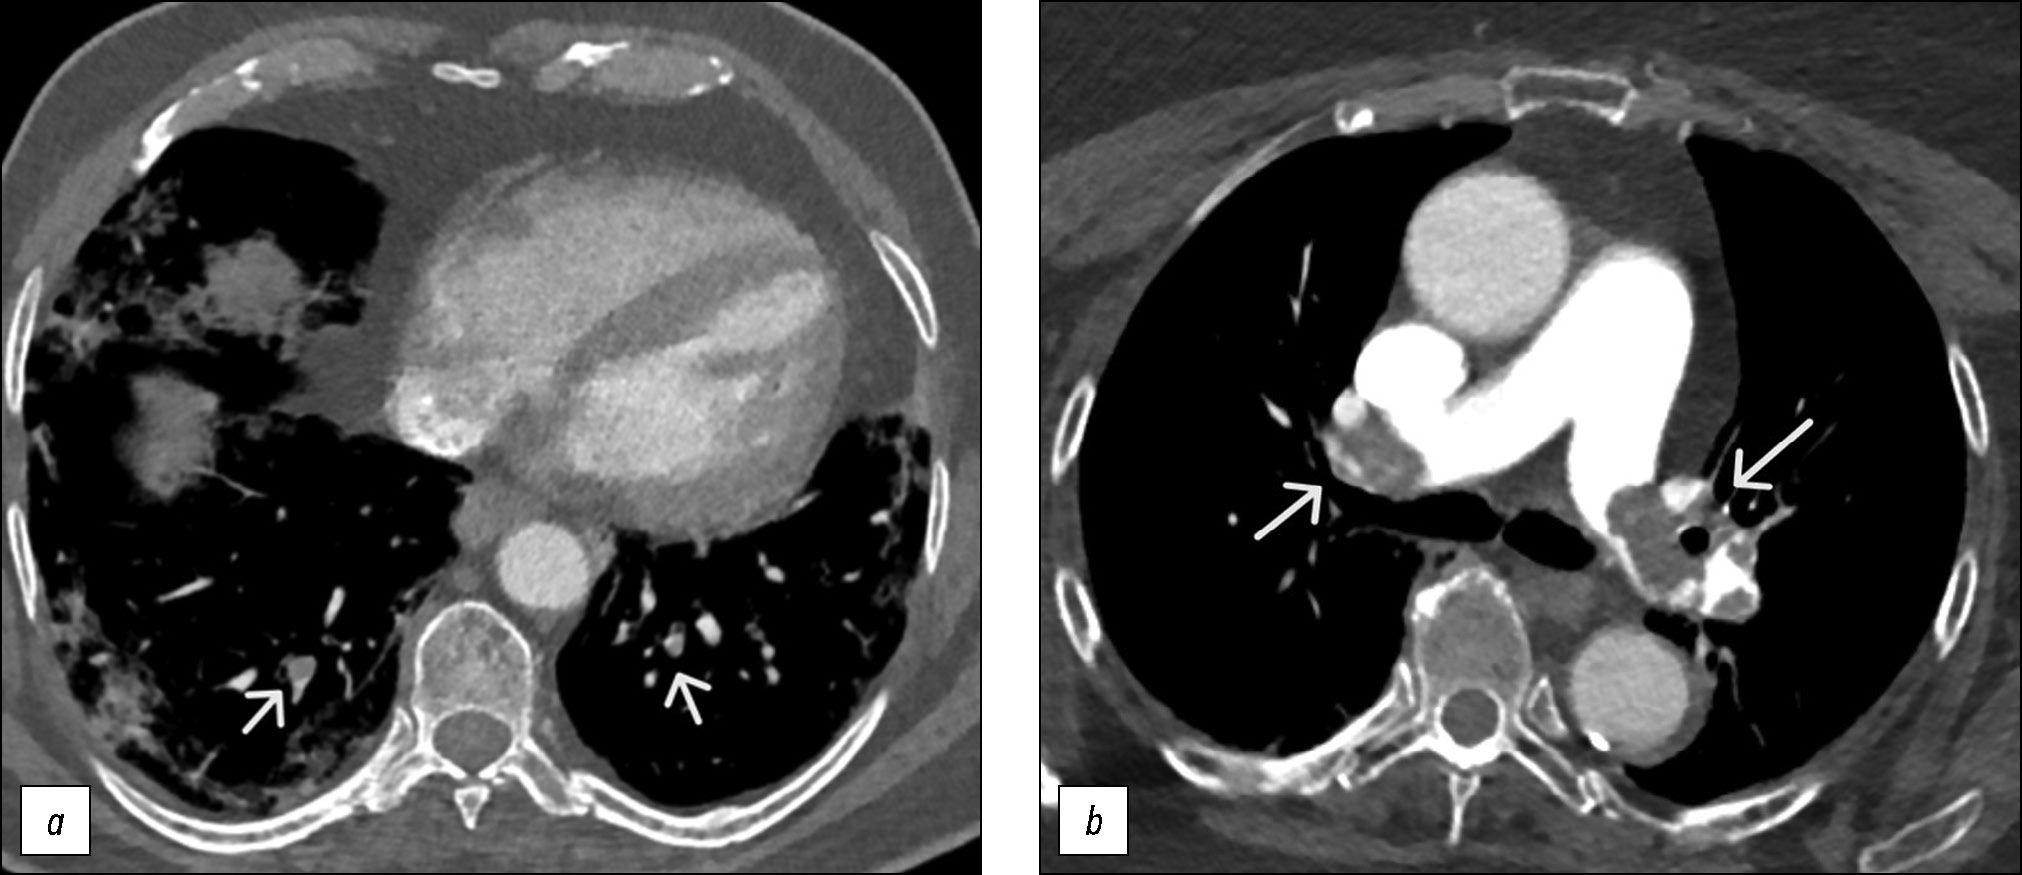

Клиническая картина пневмонии при положительном ПЦР-тесте на COVID-19 и результатах анализа D-димера >3000 нг/мл представлена на рис. 2. Отличительным критерием является наличие признаков тромбоза глубоких вен нижних конечностей (рис. 2, b) и их отсутствие (рис. 2, a) по данным УЗИ.

Рис. 2. Мультиспиральная компьютерная томография-ангиография при тромбоэмболии лёгочных артерий: a — тромбоз периферических ветвей лёгочных артерий (короткие стрелки), b — массивная тромбоэмболия главных лёгочных артерий (длинные стрелки).

Fig. 2. Multislice computed tomography angiography in pulmonary embolism: a, thrombosis of peripheral branches of the pulmonary arteries (short arrows); b, massive embolism of the main pulmonary arteries (long arrows).